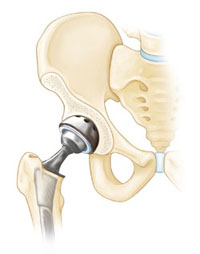

- Ολική αρθροπλαστική ισχίου

Εάν η οστεονέκρωση έχει φτάσει να προκαλέσει καταρευση της μηριαίας κεφαλής ή έχει ήδη δημιουργηθεί αρθρίτιδα τότε η ολική αρθροπλαστική του ισχίου είναι η καλύτερη επιλογή. Εξαφανίζει τον πόνο και αποκαθιστά την κινητικότητα της άρθρωσης.